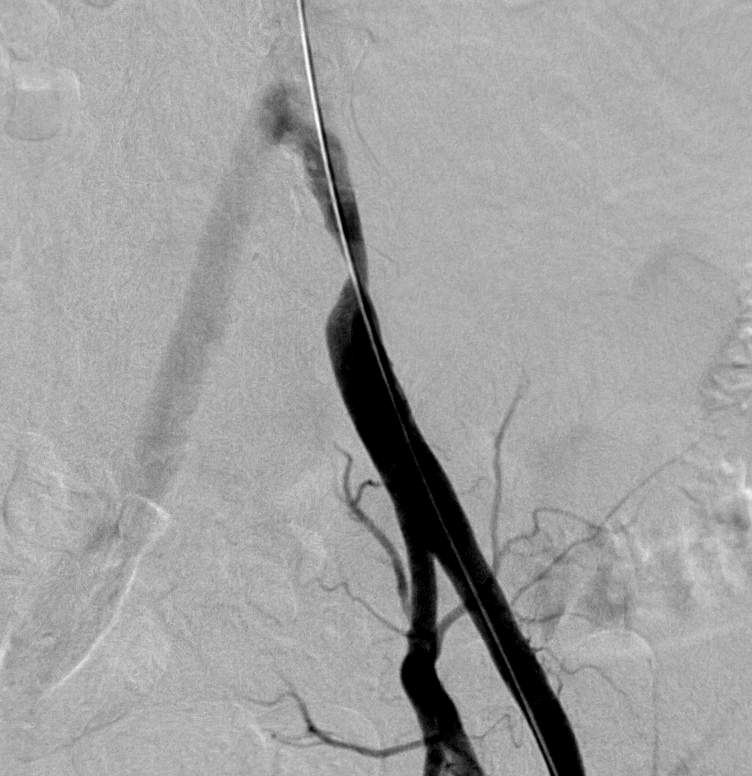

Due to technical reasons (antegrade or retrograde puncture, contralateral or ipsilateral puncture, femoral or brachial puncture), prognosis and risks, three types of levels are distinguished: iliac (Figure 4), femoro-popliteal (Figure 5) and crural (infragenual) (Figure 6) endovascular therapy. The latter two composes the infrainguinal group. PTA and stent placement are usually technically easier (with the exception of long occlusions), have a longer patency and carry lower risk in the iliac group compared to the other two groups. Patency following crural PTA is the worse and carries the highest risk, therefore, it is usually indicated only in Fontaine stages III and IV. The number of amputation per capita in Hungary is larger than that in most other European countries. In patients with gangrene and diabetes mellitus, crural PTA may save a large number of amputations. In case of successful PTA, limb salvage rate is considerably higher than crural patency rate, since perfusion needed for a healing ulcer or gangrene is considerably higher than for the basic functions (collateral arteries may be sufficient for such purpose). Subintimal PTA is performed more and more frequently: when luminal recanalisation is technically not possible, intentional dissection is done using the hydrophilic guidewire along the occluded segment; then, distally to the occlusion, the guidewire is directed back to the normal lumen and a new channel is formed along the normal lumen–dissected channel–normal lumen route (Figure 5).

Figure 5. Subintimal percutaneous transluminal angioplasty (PTA). Panel A: Superficial femoral artery has been occluded from its origin with a stump (upper arrow). Refilling occurs at the distal SFA (lower arrow), total length of the occlusion is approximately 18 cm. Panel B: The white background („roadmap”) shows the profunda femoral artery. The guidewire (in black on the white background; arrow) is at the beginning of the occluded segment. Panel C: the guidewire forms a loop (arrow), and gradually proceeds into the subintimal space. Panel D: the tip of the guidewire reached the normal popliteal artery lumen, there is no loop formation any longer. Panel E: Following balloon dilation of the whole segment, SFA shows quick flow in its entire length.